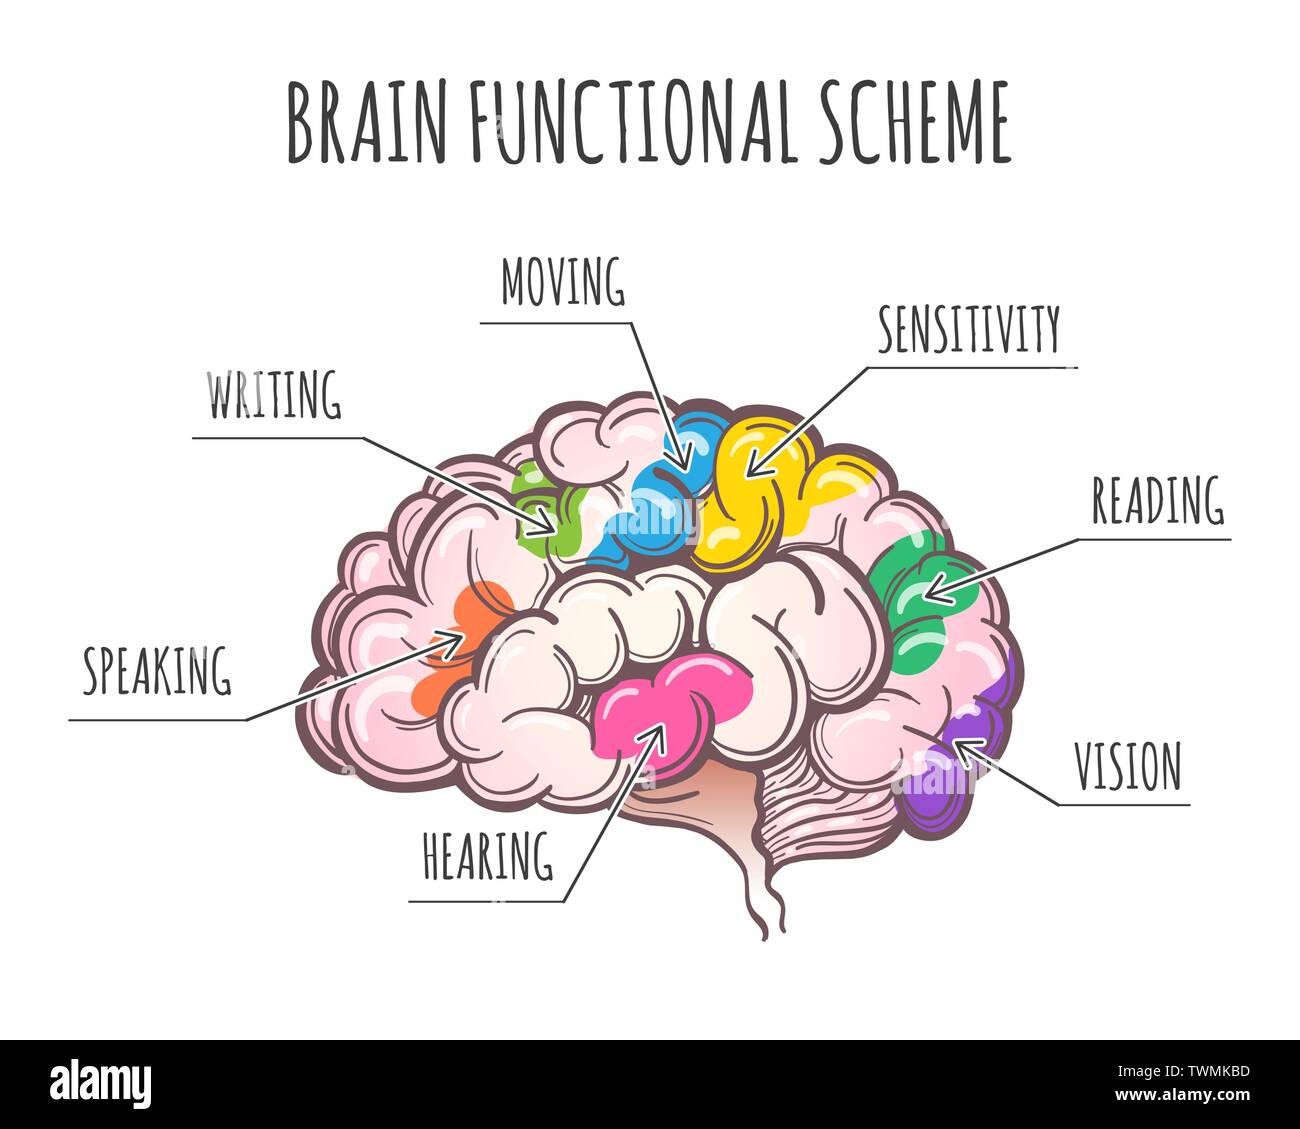

RFTWMKBD–Aree funzionali del cervello umano. Assegnazione di aree in vista laterale del cervello. Illustrazione Vettoriale